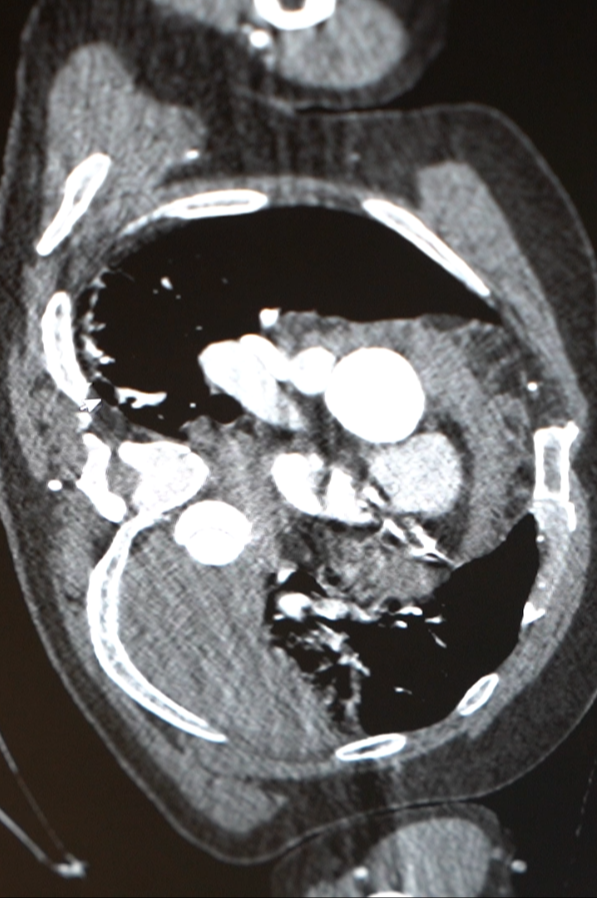

急诊检查结果不容乐观:胸腹主动脉夹层伴胸腔大量积液、纵隔积液——这些积液,考虑是从撕裂的主动脉里漏出来的!

医院心脏血管外科团队紧急会诊,这虽是B型主动脉夹层,但极其凶险,而且他已出现休克表现。“主动脉夹层就像水管壁分层开裂,一旦完全破裂,血液会瞬间涌入胸腔,没有任何抢救机会。他这种情况,已经是命悬一线。”心脏病院副院长张金洲语气凝重。

“当时他胸腔里的术前积血还在不断渗出,术后引流血性液体达 1700 毫升,相当于普通人全身血液的1/3。”心外ICU主任赵蕾回忆道。在长达6天的救助与护理之后,章先生终于在这场与死神的拔河中胜利了。